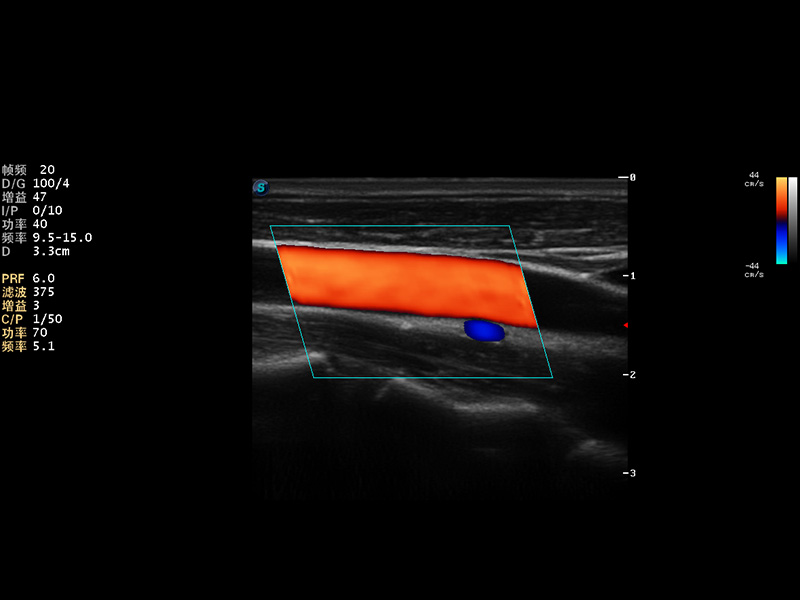

S9便携式彩色多普勒超声诊断仪是环球UG官网研发的高端便携彩超设备,外观设计新颖、产品性能卓越。S9在便携超声领域采用了突破传统的触摸屏交互设计,并以先进的软件硬件技术和设计理念,为您带来清晰的图像质量、稳定的工作性能和便捷的操作体验。

AutoC智能血流追踪